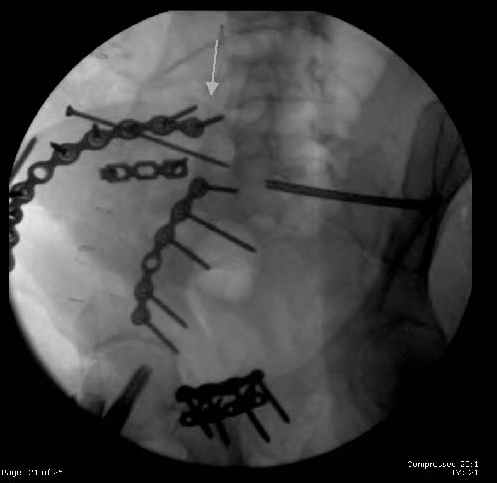

Here are the postop fluoros.

First exposed symphysis & clamped w/Faraboeuf as close to anatomic as possible.

Then extended to R ilioinguinal,really just the lateral window.

Reduced the triangular wedge piece of iliac wing to posterior intact ilium (crescent), held w/k-wire, then used 3-hole push plate to keep from moving, lagged from lat-med w 3.5 screw.

Then 6-hole plate along brim with 1 screw in R sacral ala. Then lagged 2 screws along crest A --> P. finally 10-hole plate along inner aspect of crest. R posterior ilium still a bit stepped off.

Symphysis then 'fine-tuned' & reduced as close as possible to anatomic (but, still with forward rotation of R hemipelvis - or, is it extension?) Accepted that amount of deformity and plated symph

with 4-hole symphyseal plate.

Fluoroed L SI joint and it seemed stable, but wide. So, applied c-clamp to try to squeeze down L SI joint (and note, on the last slide attached, that it's still wide), and got it closer. Single perc Iliosacral screw 40mm thread.

Applied second plate anteriorly on symphysis as I wasn't confident L SI was as stable as it could be and wanted to protect it better.

The mal-alignment that you indicated by the arrow in your photo of the ilium, do you have some idea as to how that occurred? was the crescent component locked in such a manner that it could not be moved?

So, there I was with the aforementioned info on my mind, and my R iliac wing was a little malreduced. I think it's in residual extension and some external rotation, explaining the 5-6mm gap/step

on the posterior R iliac wing. (When I loooked at the inlet fluoro, the L obturator foramen was more visible than the R obt foramen, as was the R ischial spine) so it's not as stable as if it were

anatomic, despite all the metal. This came from hesitance to take down all the posterior paraspinals to really see the R posterior crest (where the malreduction is best seen on the iliac oblique view), and I could see the entire iliac fossa and most of the crest anyway.